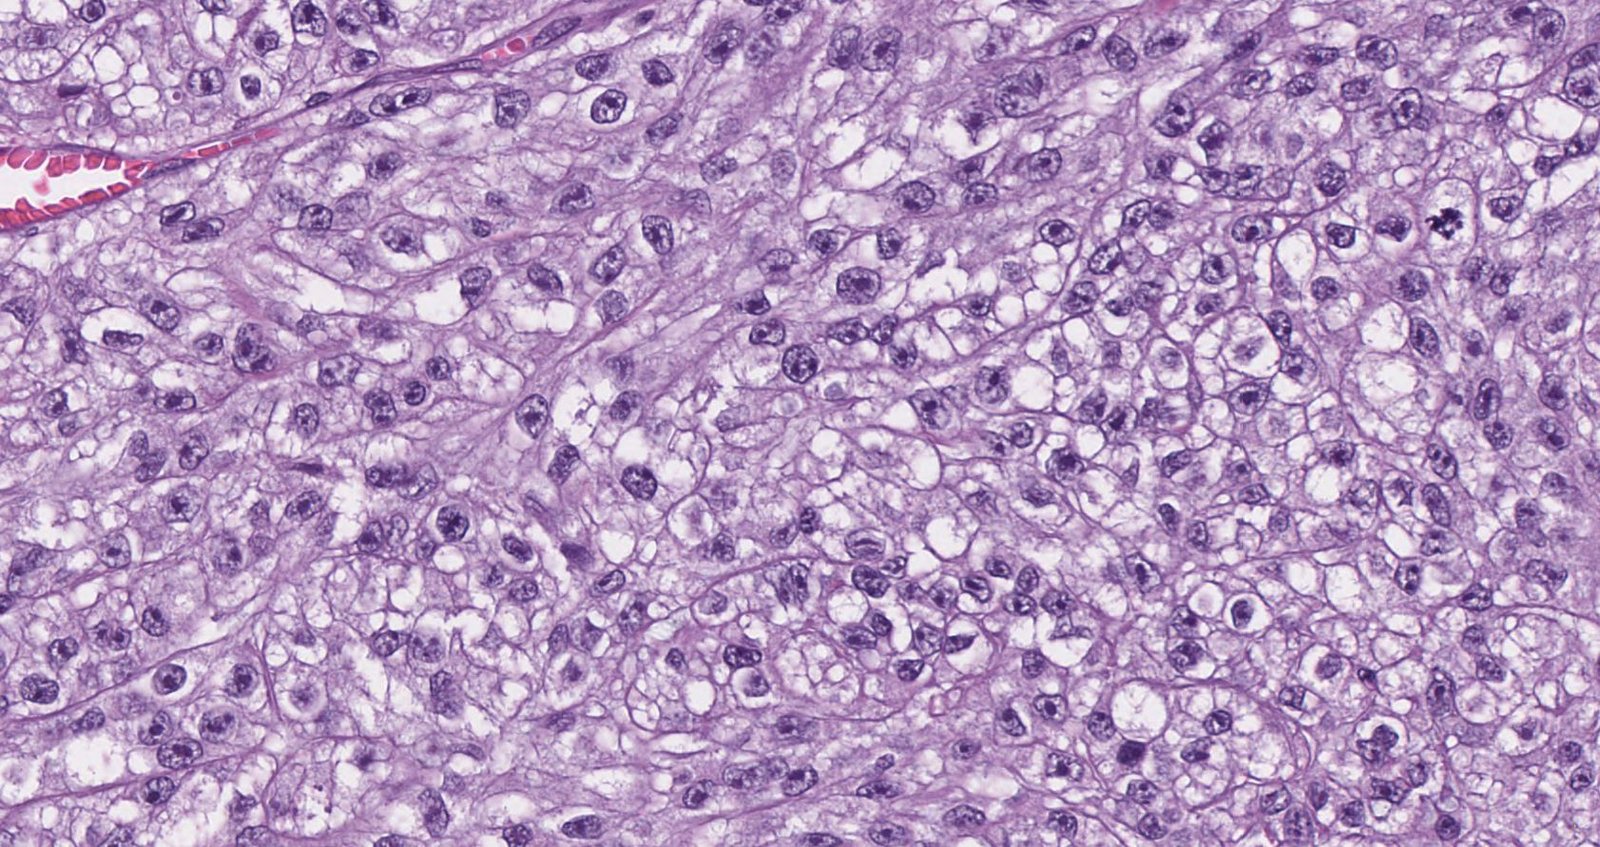

Case: TendonMass

Final Diagnosis: